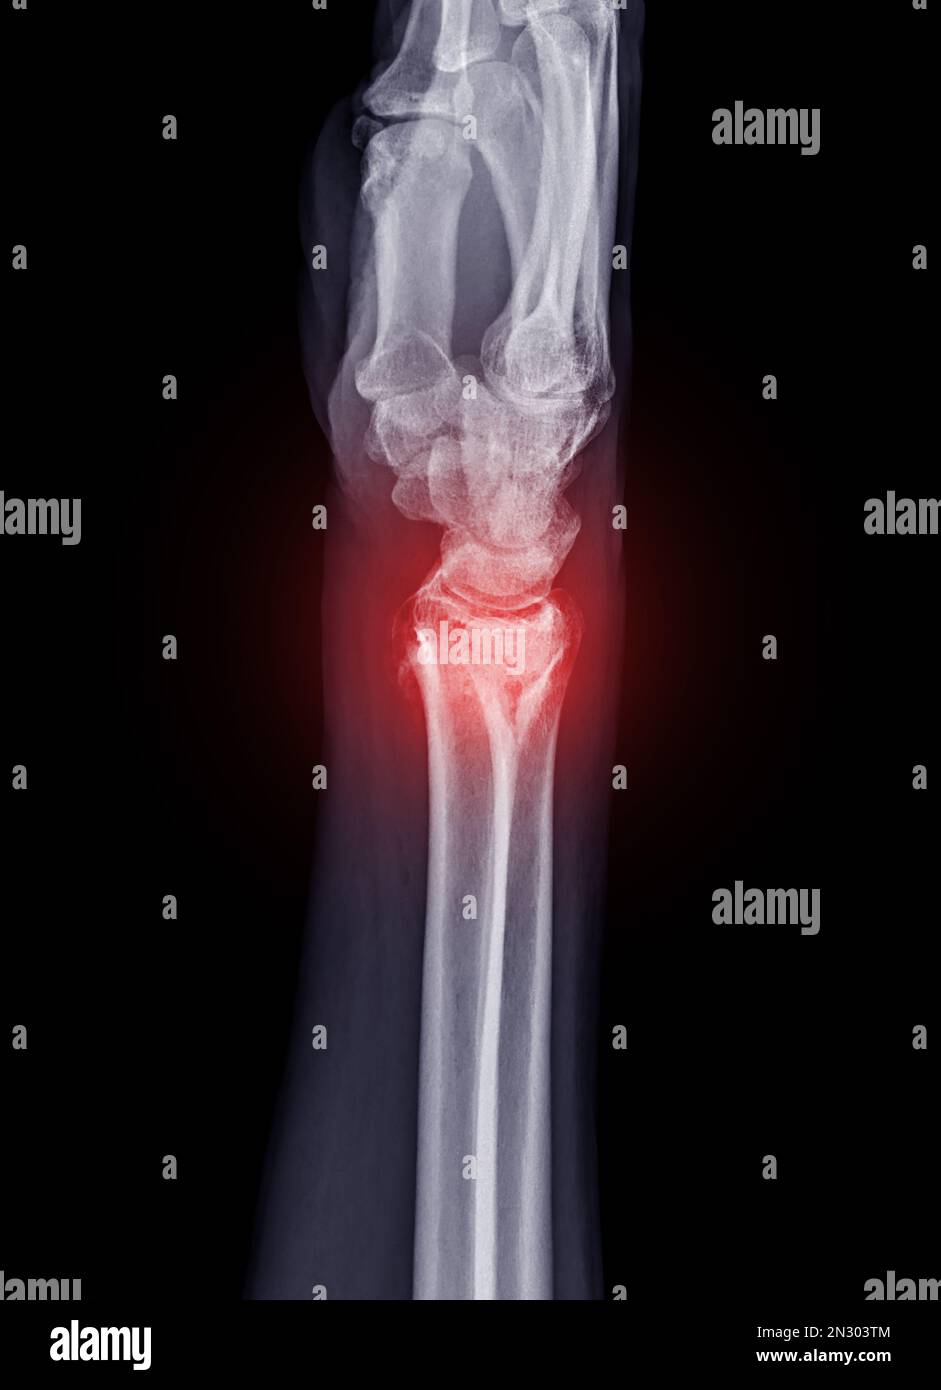

X Ray of human hand with broken wrist, fracture of radius, xray Wrist Joint Fracture X Ray This article provides a comprehensive approach to wrist radiographs, including techniques and common indications for imaging. Assessment of a wrist fracture must also include a description of the distal ulna and distal radioulnar joint (9). The articular surfaces of the proximal and distal carpal rows should form three smooth arcs. The spacing between all carpal. The distal ulna articulates with. Wrist Joint Fracture X Ray.

Film Xray Wrist Joint Showing Fracture of Ulnar Bone Isolated on Black Wrist Joint Fracture X Ray Trace these arcs on the ap film. The scaphoid bone is the most commonly fractured wrist bone. The spacing between all carpal. The articular surfaces of the proximal and distal carpal rows should form three smooth arcs. Important fractures around the wrist. Distal radial fractures can occur at any age but are particularly common in older women because of osteoporosis,. Wrist Joint Fracture X Ray.

Film xray Wrist joint showing fracture of ulnar bone isolated on black Wrist Joint Fracture X Ray The articular surfaces of the proximal and distal carpal rows should form three smooth arcs. Assessment of a wrist fracture must also include a description of the distal ulna and distal radioulnar joint (9). Trace these arcs on the ap film. The scaphoid bone is the most commonly fractured wrist bone. Important fractures around the wrist. The spacing between all. Wrist Joint Fracture X Ray.

Film xray Wrist joint showing fracture of ulnar bone isolated on black Wrist Joint Fracture X Ray Distal radial fractures can occur at any age but are particularly common in older women because of osteoporosis, which warrants. Assessment of a wrist fracture must also include a description of the distal ulna and distal radioulnar joint (9). The distal ulna articulates with the sigmoid notch of the radius. Stable nondisplaced fracture (majority of fractures) if patient has normal. Wrist Joint Fracture X Ray.